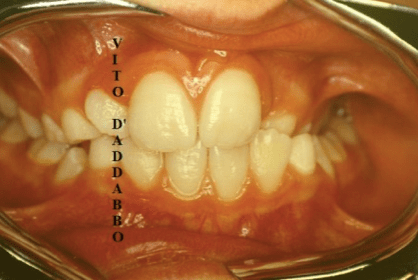

In una bocca che chiude correttamente i denti dell’arcata superiore sono collocati più esternamente rispetto ai corrispondenti dell’arcata inferiore. Nel morso inverso accade il contrario: in quello laterale sono i denti inferiori laterali a chiudere esternamente.

Questa malocclusione è il più delle volte dovuta a un mascellare piccolo, come nel caso riportato, dove manca anche lo spazio per l’incisivo laterale permanente di sinistra. I morsi incrociati vanno corretti precocemente perché possono provocare gravi asimmetrie del viso.

prima